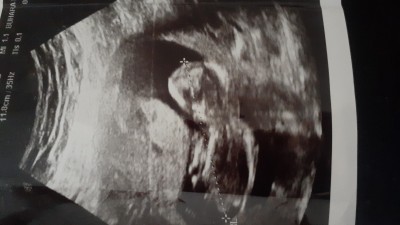

Cinsiyet tahmininde bulunun kızlar.lütfen kırıcı yorum yapmayın merak sadece .

Gebelik haftası 13